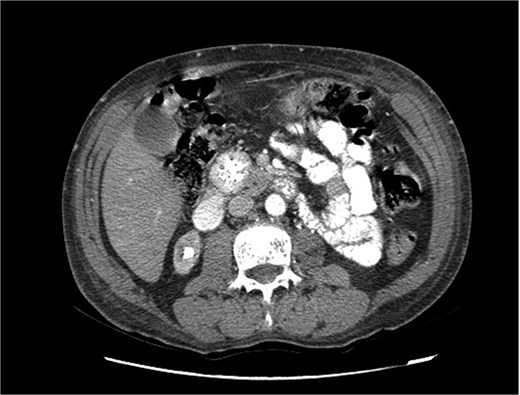

Upon admission in January 2025, the patient presented with altered mental status, dehydration, and hypoglycemia. The recurrence of hypoglycemic episodes was confirmed by laboratory studies and imaging, which identified a well-defined 3 cm mass in the pancreatic head on triphasic computed tomography (Figs 1–3). Given the diagnosis of recurrent malignant insulinoma and the possibility of resection, a surgical approach was chosen.

Triphasic computed tomography of the pancreas, late phase, showing a tumor in the head of the pancreas.